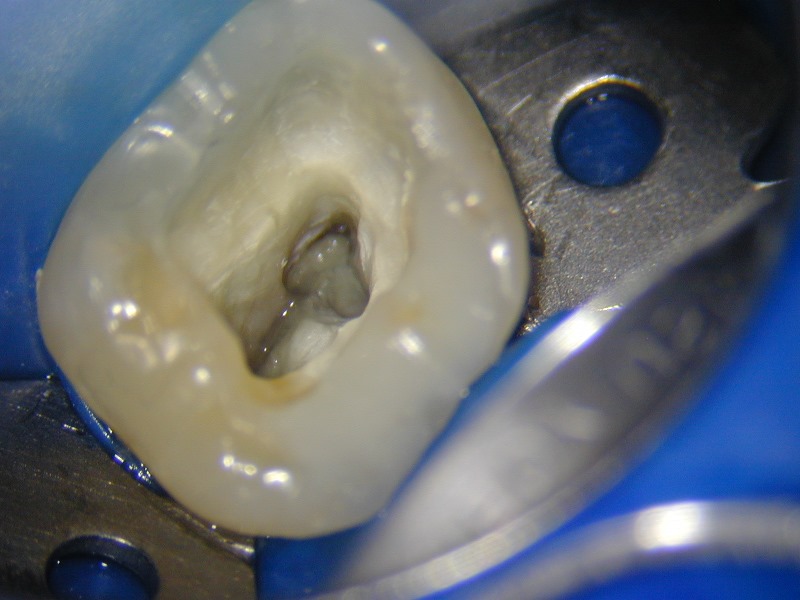

O microscópio operatório para odontologia foi desenvolvido para que pudéssemos ter a visibilidade necessária para detectarmos a entrada dos canais radiculares que recobertos por dentina ou por detritos nos impediam a completa descontaminação dos canais radiculares. Com ele também visualizamos e amplificamos a imagem para detectar possíveis trincas, fraturas ou calcificações que impedem o tratamento. Observem as fotos dos casos clínicos que mostram como conseguimos trabalhar e fotografar os casos com a máquina acoplada ao MO.

Foto da câmara pulpar com nódulos impedindo a entrada e acesso ao canal radicular.